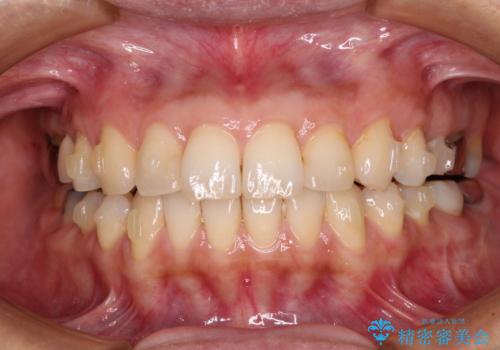

後戻りは軽微であったため、インビザライン・ライトにて歯列を整えました。

矯正治療後のレントゲン写真では、根尖部に認められた病変(骨の溶けていた像)は消失していることが分かりました。